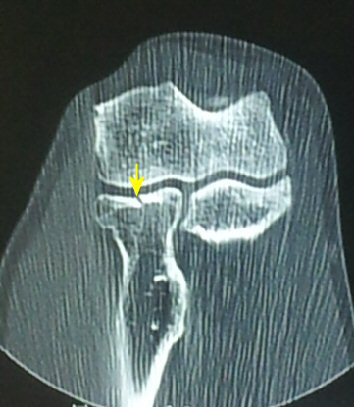

°ËÇ»ÅÍ ÃÔ¿µ : ¿ä°ñ µÎ ÀåÃà¸é °ñÀý( ±×¸² 6. 7)